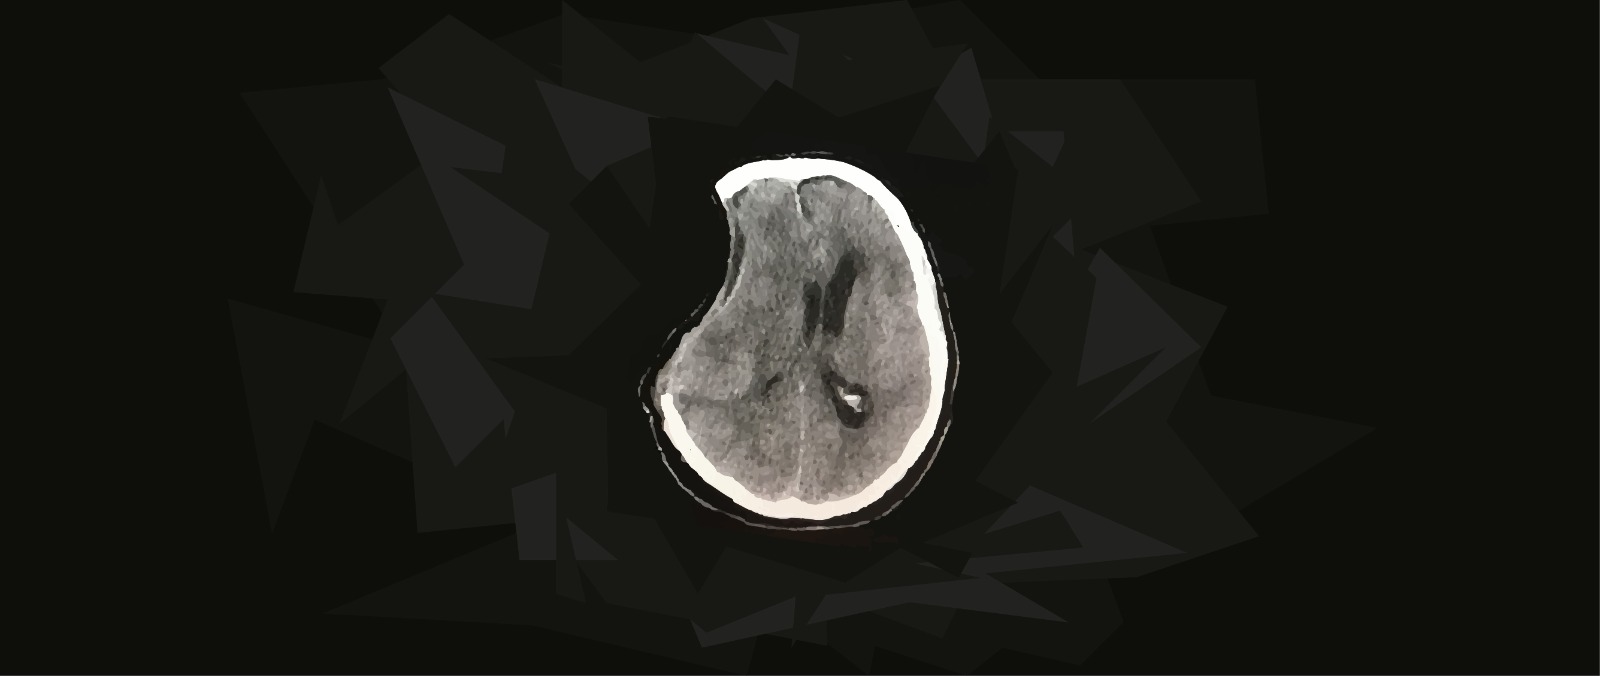

Después de una recuperación inicial alentadora, su condición comenzó a deteriorarse repentinamente después de 2 meses, lo que se manifestó en síntomas neurológicos y cognitivos negativos. Además, se registró un defecto en el cuero cabelludo y la tomografía computarizada mostró signos de hidrocefalia.

Si bien los síntomas característicos pueden ser suficientes para obtener un diagnóstico, también pueden identificarse otros signos que coinciden con esta afección. Así, desviaciones de las estructuras mediales cerebrales, herniación, hundimiento del cuero cabelludo y profundización de los surcos cerebrales suelen estar asociados a la patología. En este sentido, suelen utilizarse técnicas de radiografía como la tomografía computada (computed tomography, CT, en inglés) y resonancia magnética (magnetic resonance imaging, MRI, en inglés) para evaluar dichos aspectos.

Por otro lado, niveles alterados de líquido cefalorraquídeo pueden ayudar a predecir la ocurrencia eventual del síndrome. Y es que, se han observado patrones de ocurrencia de síndrome del trepanado en personas que presentan menor volúmen de líquido cefalorraquídeo, específicamente en el tercer ventrículo cerebral (Vasung et al., 2016).